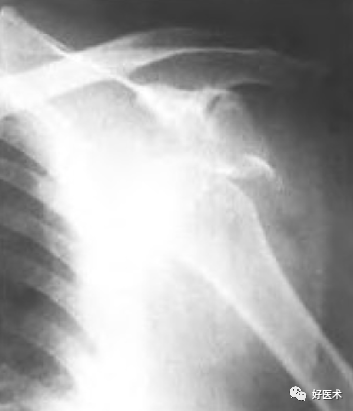

肱骨外科颈骨折 无移位型

外科颈骨折 外展型

外科颈骨折 内收型

外科颈骨折 伸展型

解剖颈骨折

大结节骨折

合并肩关节半脱位,大结节撕脱性骨折

合并肩关节脱位的大结节骨折

肩关节半脱位